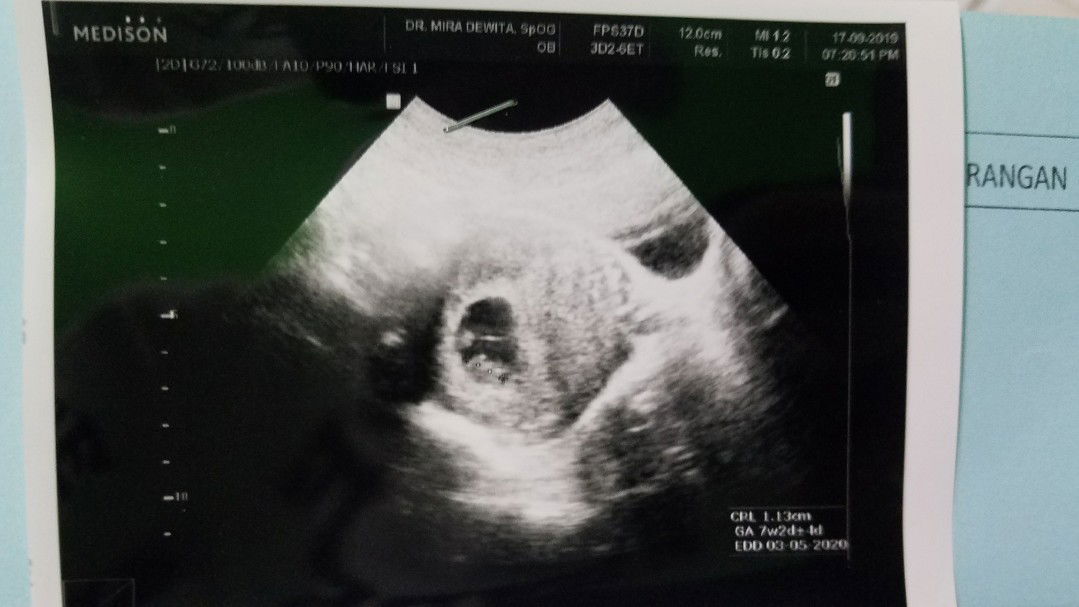

USG

bun kira2 USG ku itu keliatan kembar gak sih bun?